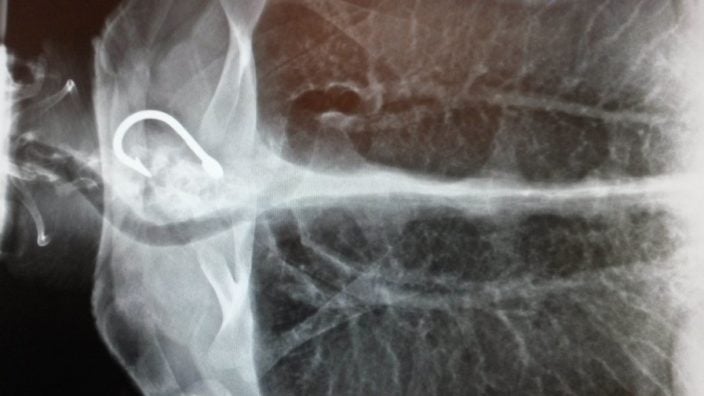

Un equipo veterinario especializado del parque Marineland se hace cargo de las tortugas y las rehabilita, para poder devolverlas al mar en cuanto su estado físico y de salud lo permite. Este esfuerzo de conservación se desarrolla bajo la supervisión del RTMMF (Réseau des Tortues Marines de Méditerranée ; «Red de totugas marinas del Mediterráneo» en español).